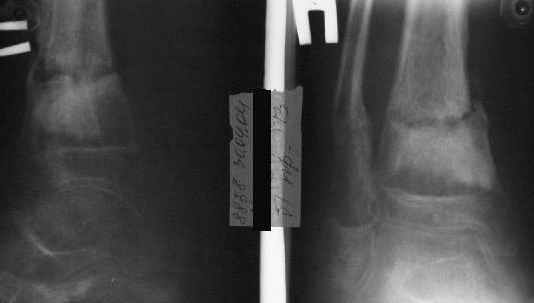

В январе 2005: варусная деформация н\3 голени, болевой с-м, комбинированная контрактура г\стопного сустава, нейропатия м\берцового нерва сохраняется слабость разгибания 1 пальца.

Операции: 1 Клиновидная резекция на вершине деформации м\берцовой кости.

2 Тугоподвижный ложный сустав н\3 б\берцовой кости. Рубцы выполняющие пространство между отломками, канал проксимального отломка иссечены.

Одномоментное устранение деформации, остеосинтез Г-образной пластиной.

На данный момент ходит при помощи костыля (без присмотра -без костыля :), разрабатывает движения в г\стопном суставе.

AVM> А каково у него укорочение голени?

В пределах 2 см.

Не катастрофа. Рост продолжается, будем следить в динамике.